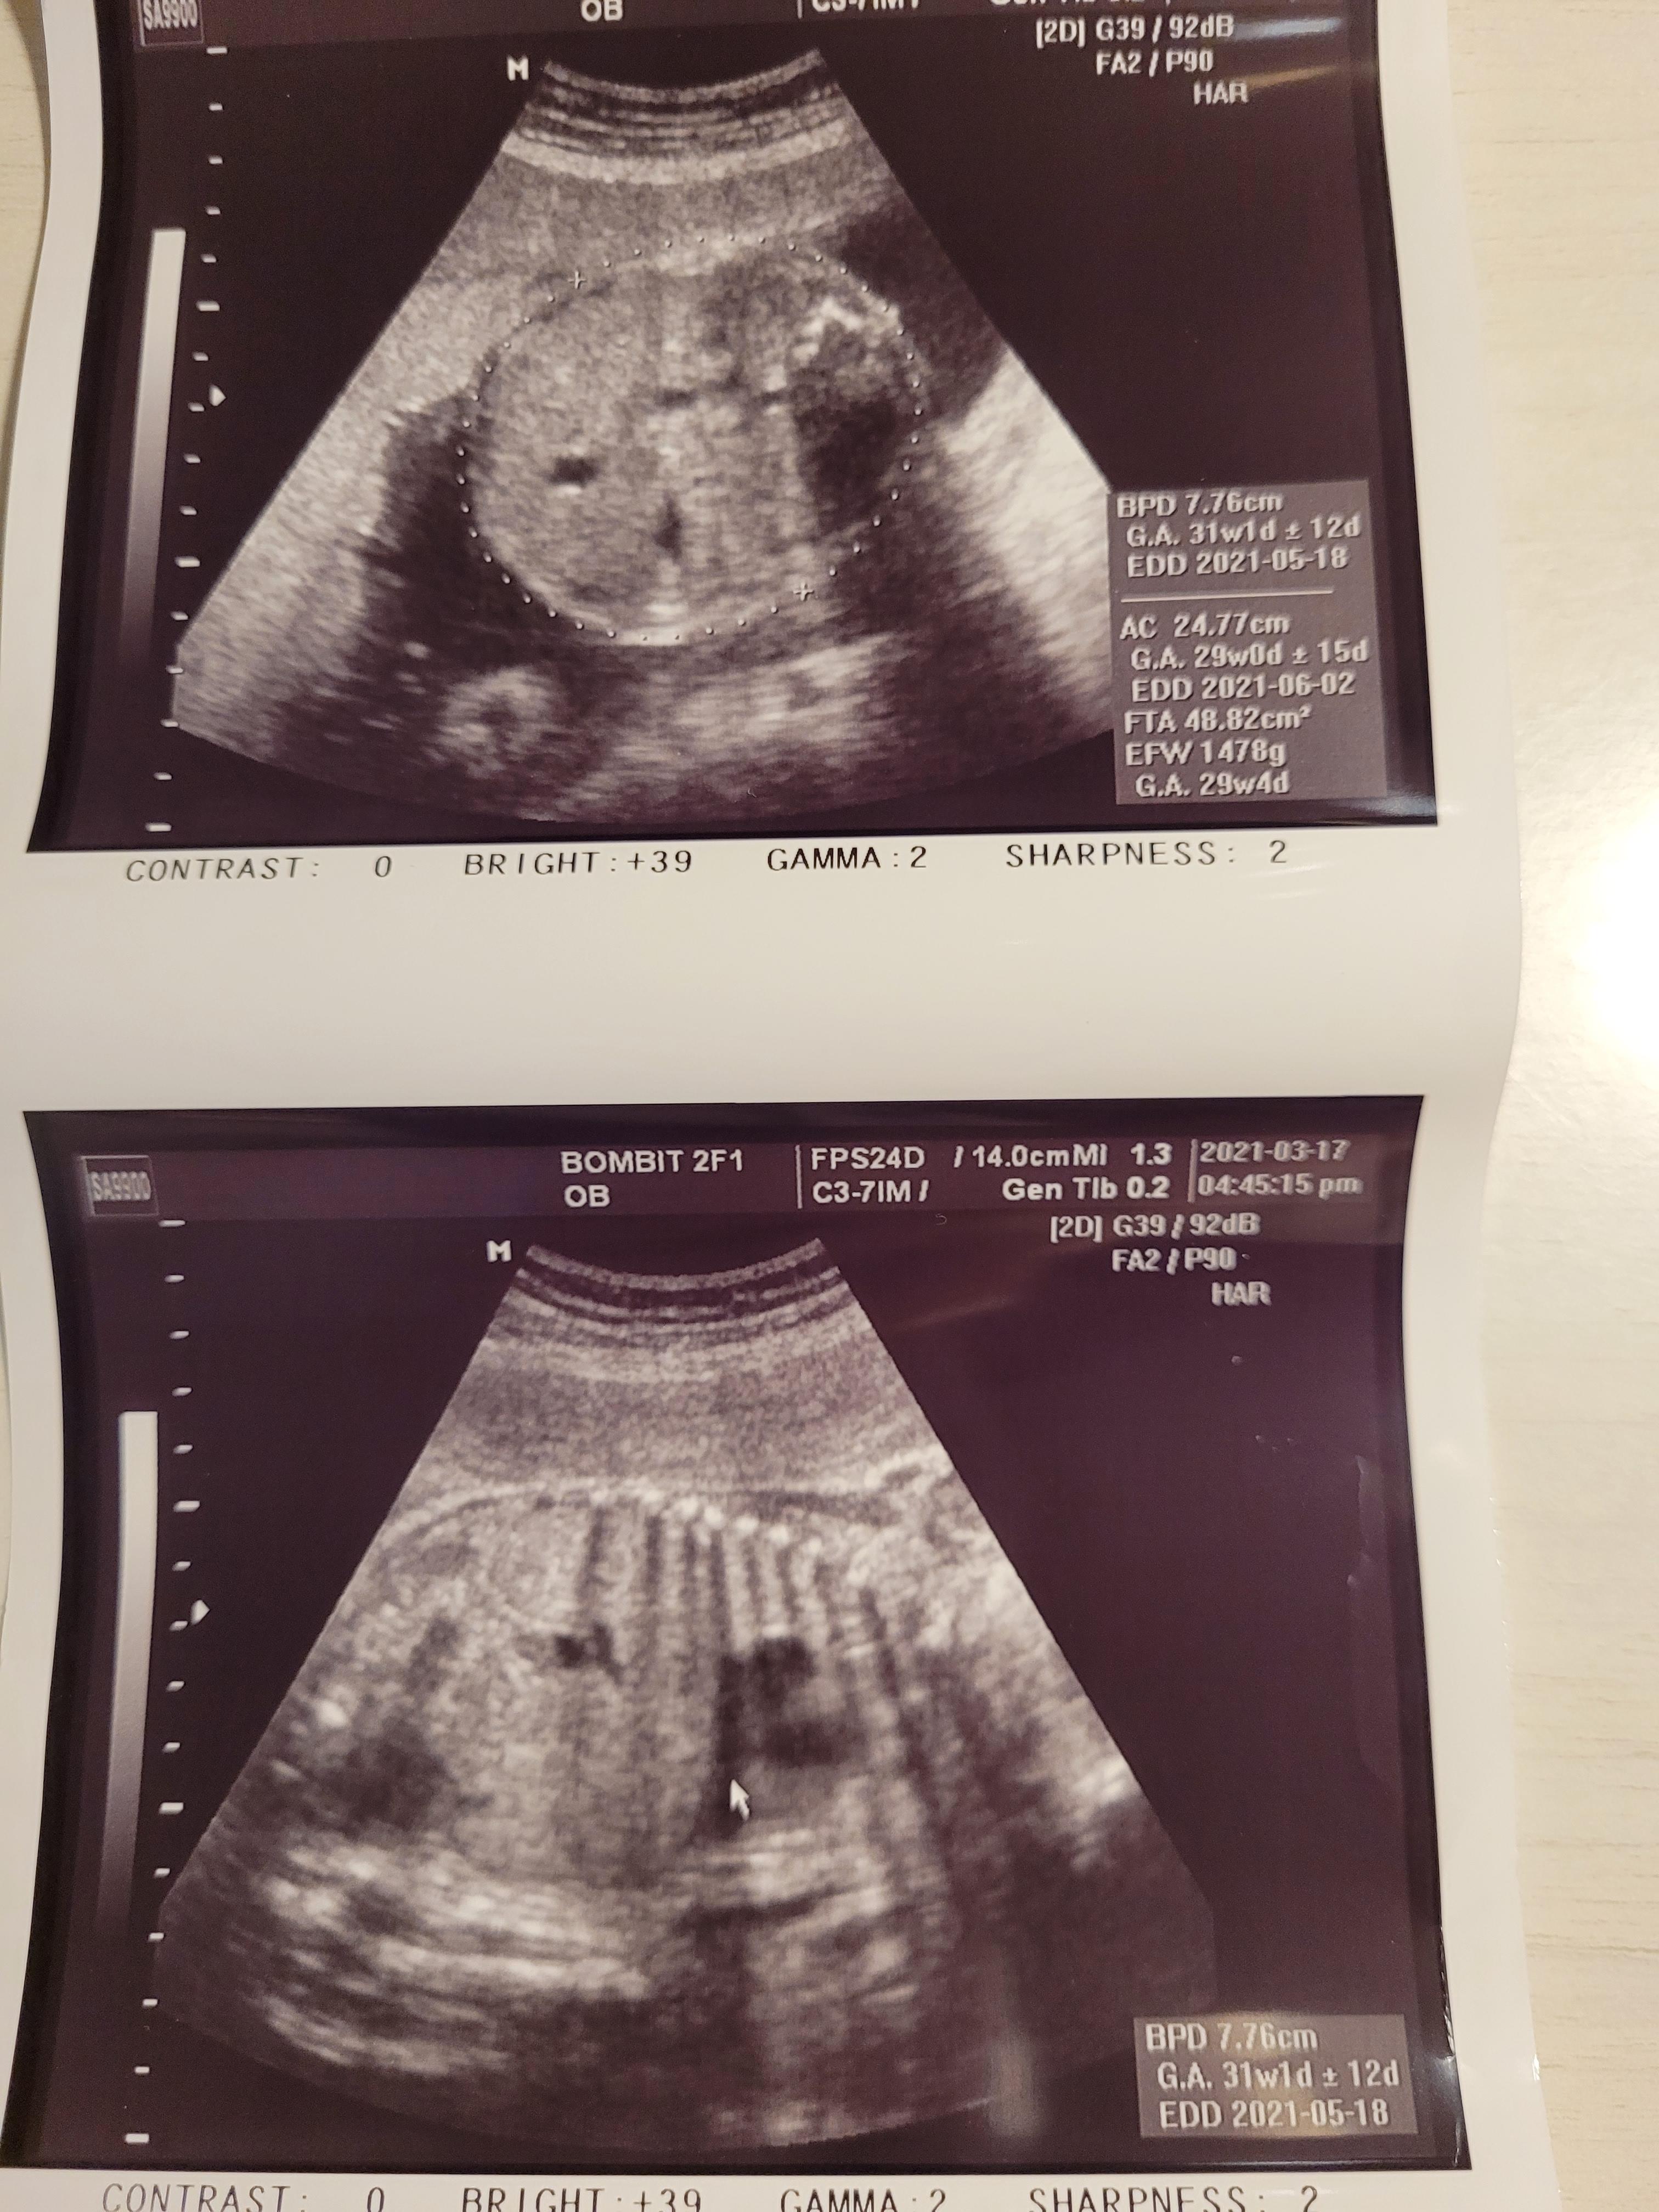

머리크기는 이미 31주가 넘어간 우리 행복이..

잘 크고있어서 다행인데, 너무 크면 나중에 출산할때 힘들것같더라고요.

양수도 넉넉하고, 아기도 잘 크고있어서 한시름 놓았어요.